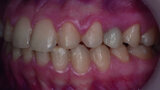

Orthodontic management of maxillary lateral incisors agenesis